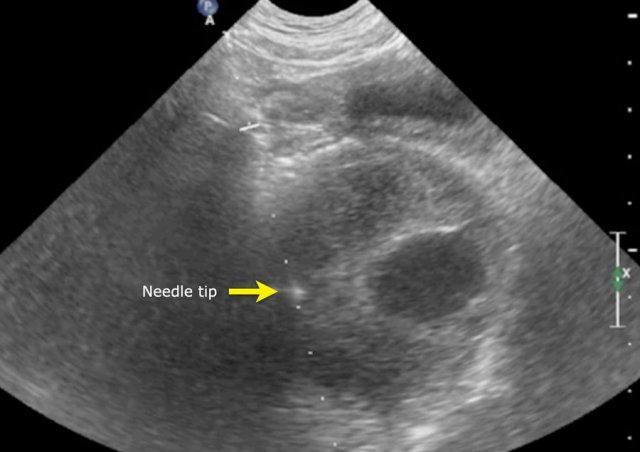

Biopsy

Percutaneous biopsy can be difficult for two reasons:

- Những khối u này chứa nhiều mô hoại tử dẫn đến chỉ còn lại chất nhầy và không thể chẩn đoán giải phẫu bệnh

- Những khối u này có thể chảy máu nhiều trong quá trình sinh thiết. Sinh thiết mở có thể là cần thiết, nhưng phương pháp này cũng có thể đi kèm với chảy máu nhiều.

Hình ảnh

Hình ảnh MRI của một bé gái chín tháng tuổi có khối u ở bụng trái. MRI cho thấy khối u tuyến thượng thận trái, một phần đặc, một phần nang. Có nhiều di căn gan.

Khối u đã được sinh thiết. Có tình trạng chảy máu liên tục qua kim dẫn đường. Vào cuối thủ thuật, hai nút bọt gelatin đã được đặt vào (các dải tăng âm (mũi tên)).